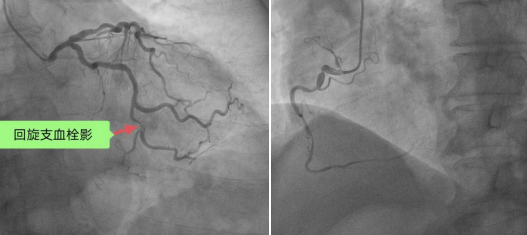

患者急诊冠脉造影图像

导丝通过,冠脉内溶栓后植入1枚支架。

术毕收入CCU病房,术后胸闷、胸痛症状完全缓解,心电图恢复正常。患者进院至血管开通只有短短的23分钟,远低于业内平均用时(60分钟)。